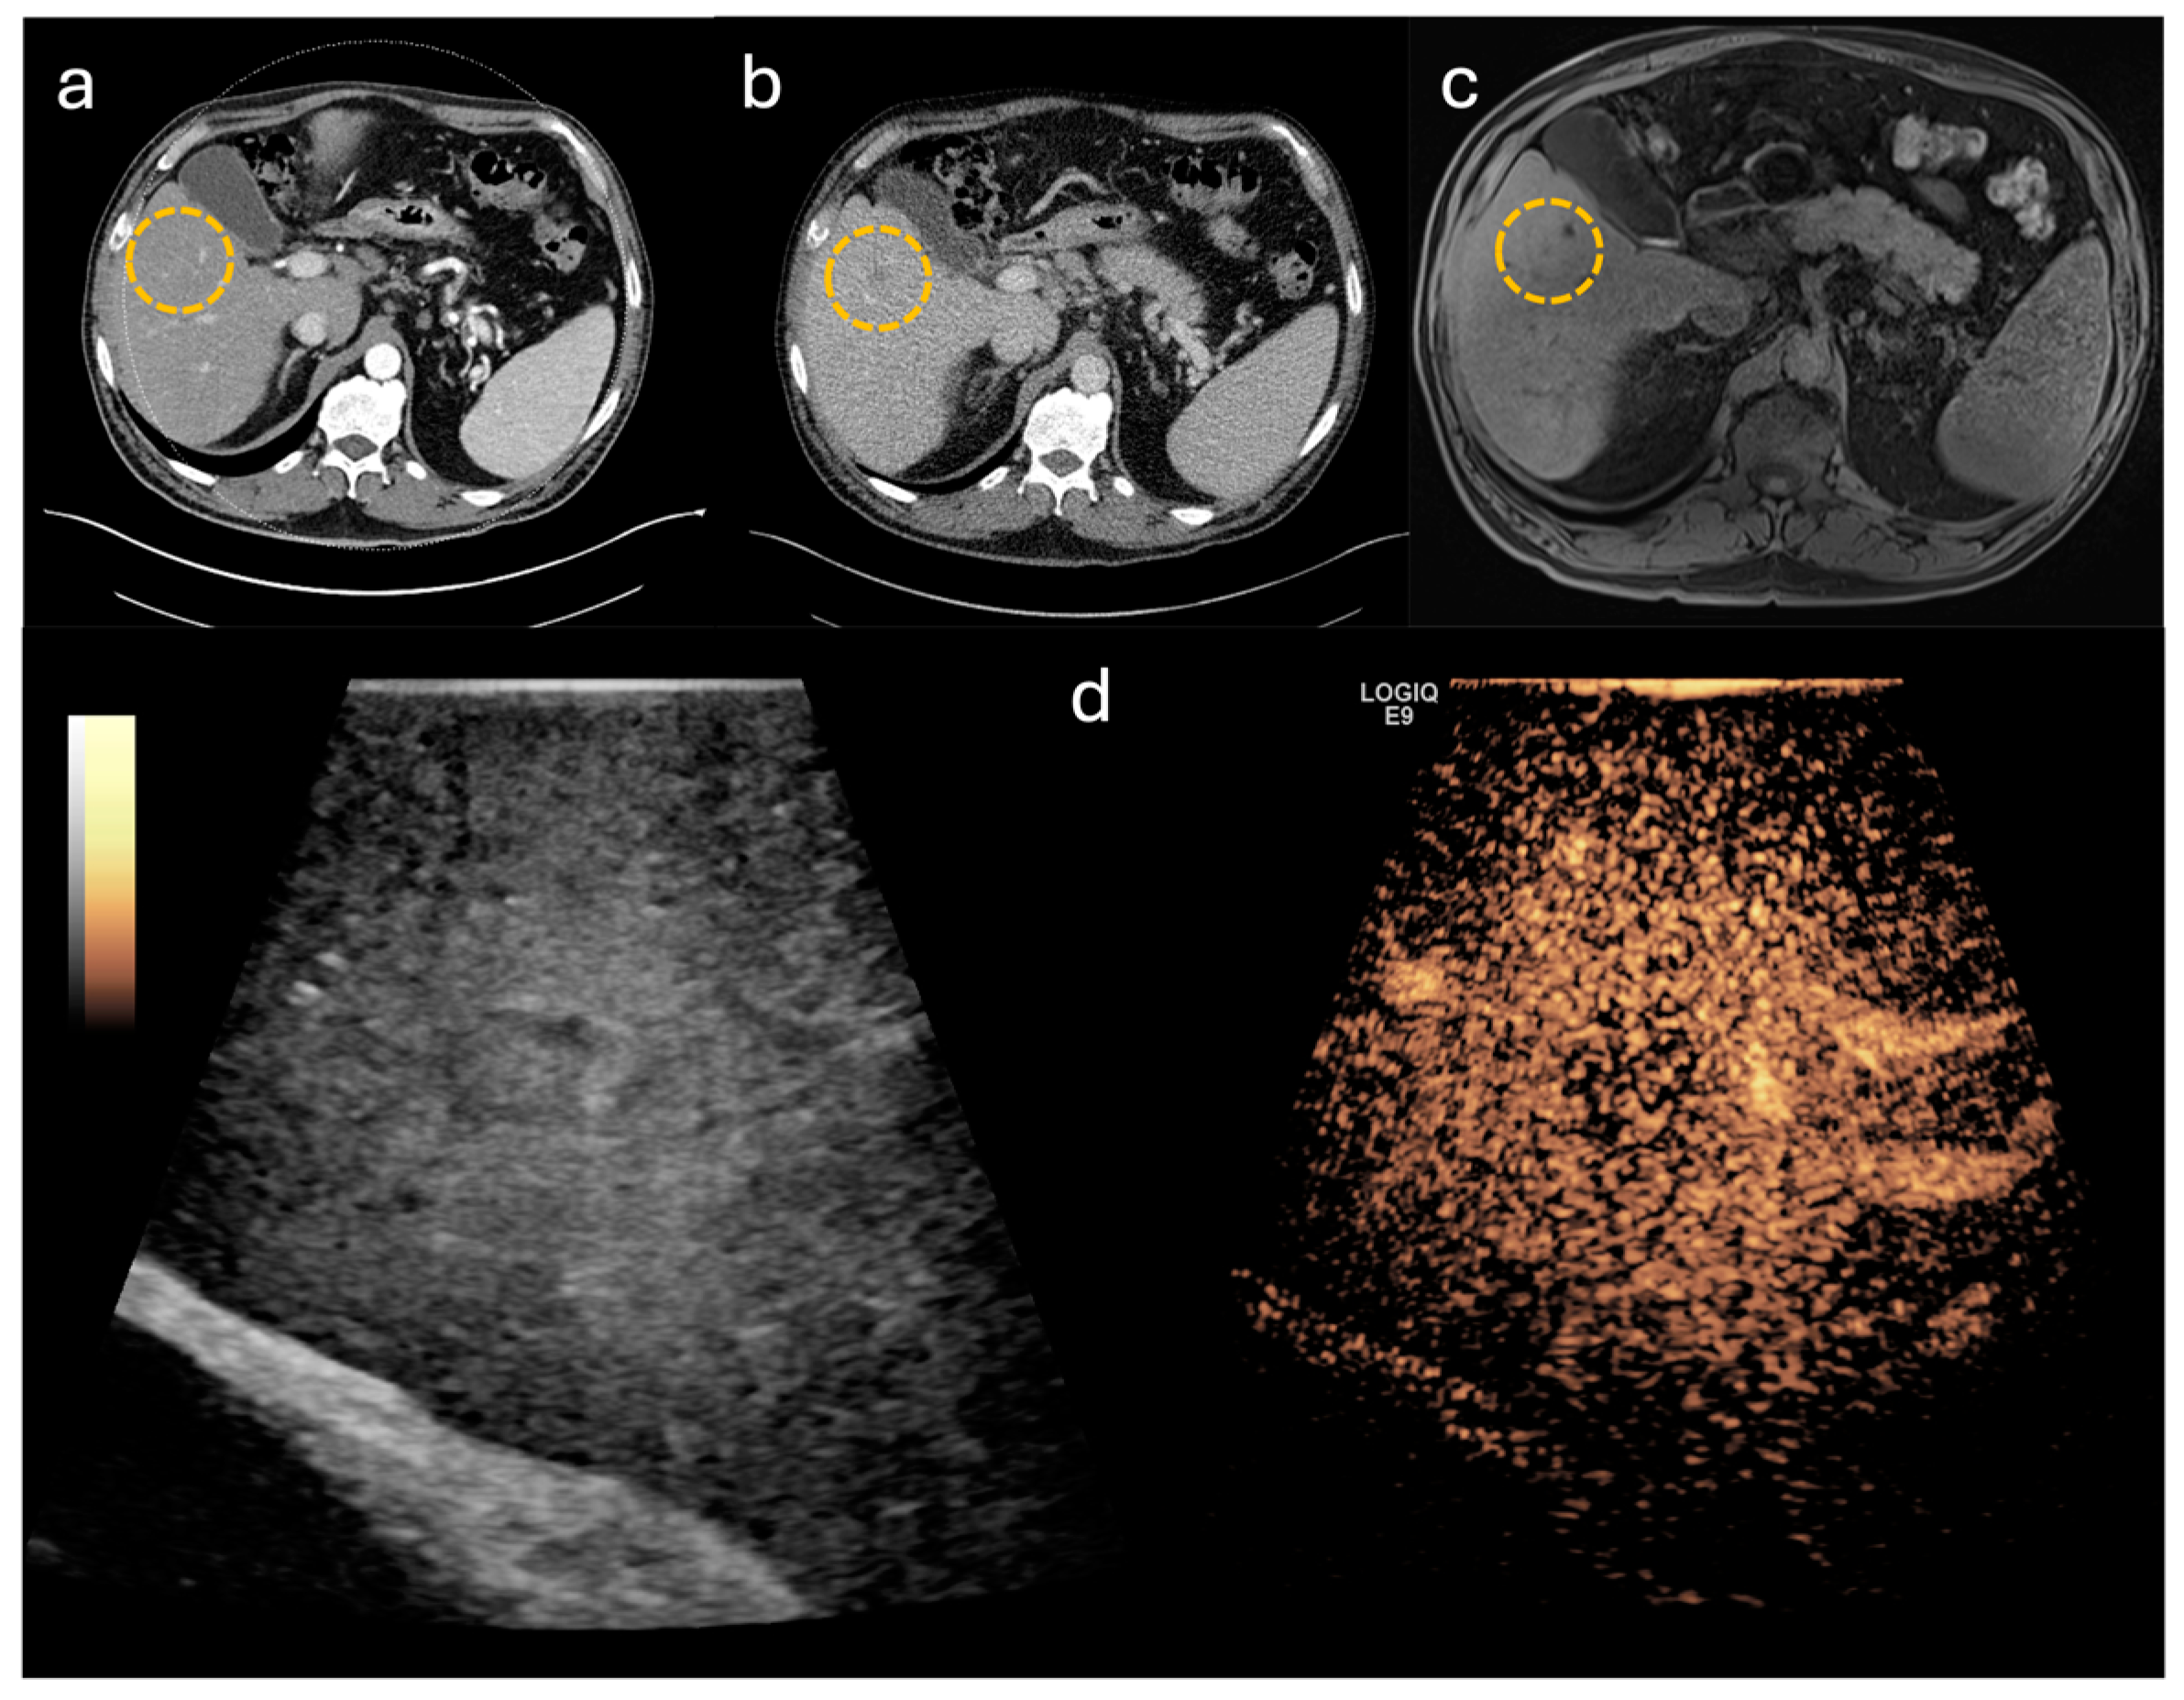

3.3. Accuracy of CE-IOUS